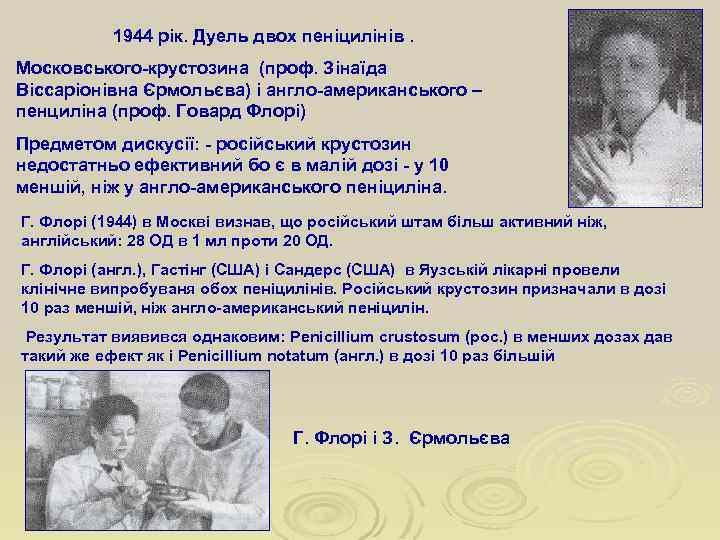

1944 рік. Дуель двох пеніцилінів. Московського-крустозина (проф. Зінаїда Віссаріонівна Єрмольєва) і англо-американського – пенциліна (проф. Говард Флорі) Предметом дискусії: - російський крустозин недостатньо ефективний бо є в малій дозі - у 10 меншій, ніж у англо-американського пеніциліна. Г. Флорі (1944) в Москві визнав, що російський штам більш активний ніж, англійський: 28 ОД в 1 мл проти 20 ОД. Г. Флорі (англ. ), Гастінг (США) і Сандерс (США) в Яузській лікарні провели клінічне випробуваня обох пеніцилінів. Російський крустозин призначали в дозі 10 раз меншій, ніж англо-американський пеніцилін. Результат виявився однаковим: Penicillium crustosum (рос. ) в менших дозах дав такий же ефект як і Penicillium notatum (англ. ) в дозі 10 раз більшій Г. Флорі і З. Єрмольєва